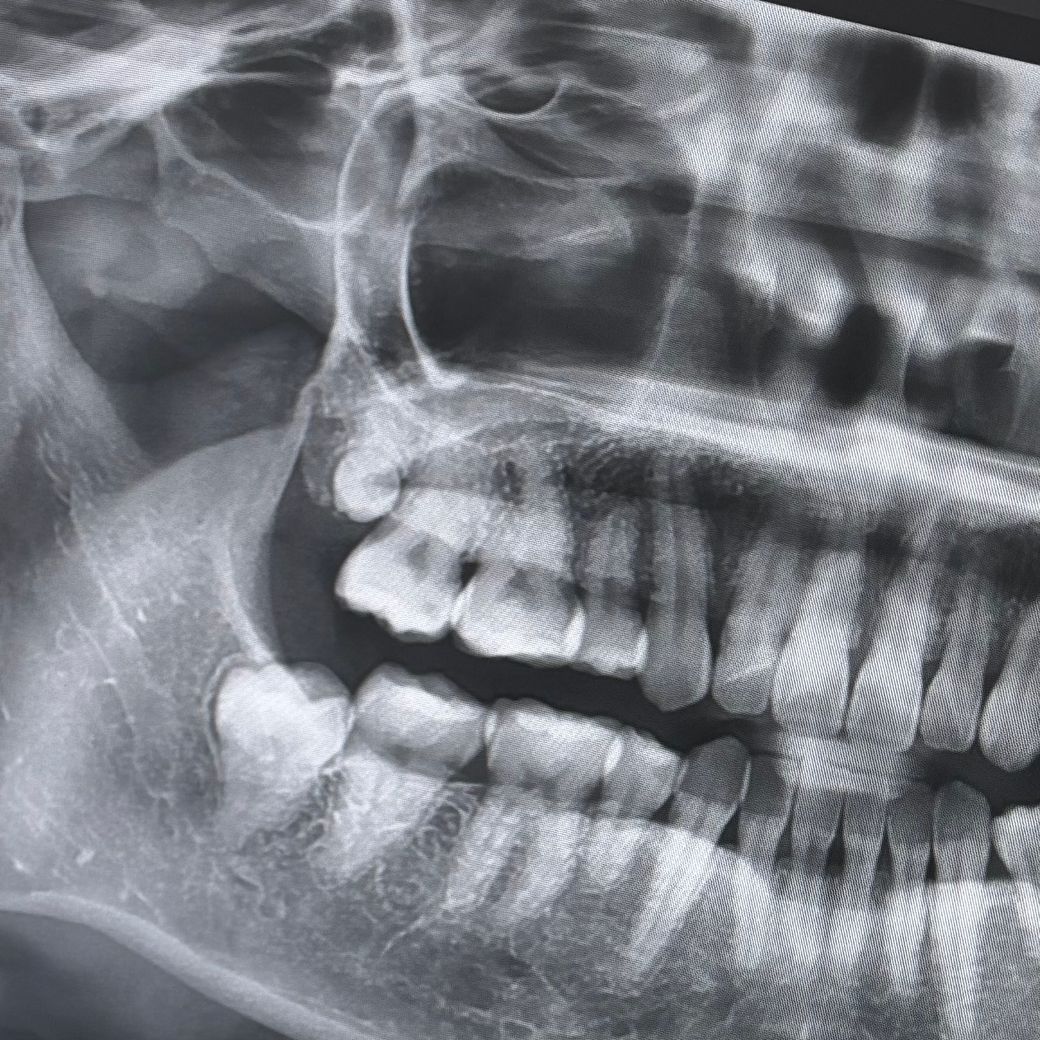

사랑니 발치 절제 범위 원래 이런건가요?

사랑니 발치 후 거울로 입안을 봤더니 사진과 같이 볼쪽까지 째서 뽑으셨더라구요. 근데 사랑니 뺀 부분만 꼬매놓으셔서 볼 쪽은 점점 더 붓고, 째진 부분이 달랑달랑 거리고 씹혀서 불편합니다. 완전 매복도 아닌데 절제 범위가 원래 이렇게 넓나요?ㅜㅜ 가만히둬야할지 약이라도 발라야할지 고민입니다..

사랑니가 위치한 게 수직이어서 그렇지 완전매복 맞습니다. 더 원활한 발치를 위해 절개를 크게 한 것 같습니다